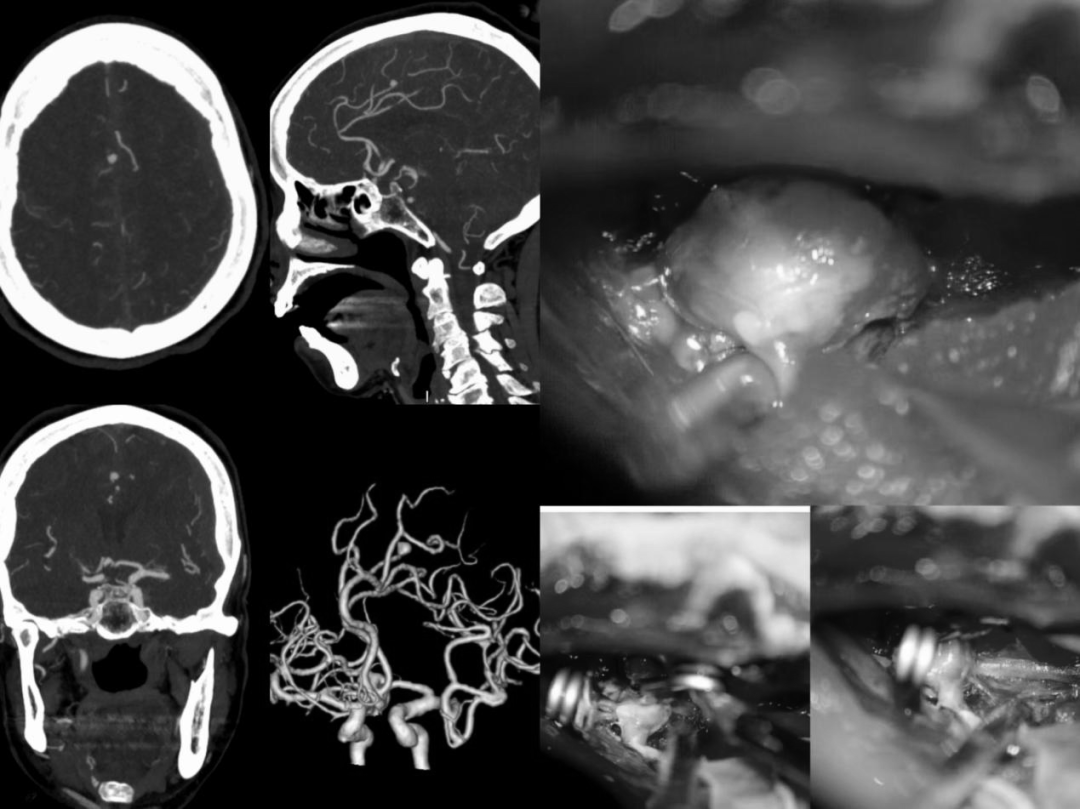

神经外科团队凭借扎实的专业功底、成熟的手术经验,精心设计最优手术方案,果断为患者实施高难度开颅手术。术中精准定位、精细操作,一次手术同步完成动脉瘤夹闭与硬膜下血肿清除,

一次性解决两大致命问题,彻底清除颅内所有隐患,手术成功。